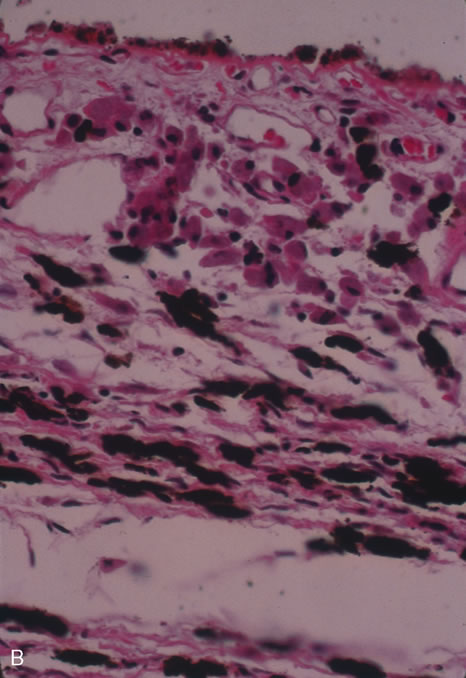

Ocular involvement most commonly occurs after reactivation in the lung or alimentary tract and is thus referred to as secondary TB (Fig. 16). Primary ocular involvement of TB is rare and is almost always limited to the cornea and conjunctiva. Conjunctival TB has been reported as a chronic unilateral conjunctivitis with a conjunctival mass or ulceration associated with regional lymphadenopathy. Although also rarely seen, conjunctival phlyctenulosis has been found to be associated with tuberculoprotein hypersensitivity. Biopsy and culture proven scleral TB was reported in the literature in 1976 and 1989. Other ocular manifestations of TB include anterior uveitis, either granulomatous or nongranulomatous, choroiditis, and choriodal tubercles/tuberculoma. A recent case series demonstrated the protean ocular findings associated with intraocular TB in addition to a variable response to antitubercular treatment.61

Fig. 16. A choroidal tubercle in a patient with miliary tuberculosis.

Classic histopathology consists of caseating granulomatous inflammation in a zonal distribution. The noncaseating tubercle may be present but is less specific (Fig. 18). The organism is acid-fast, meaning that it does not decolorize with acid alcohol after staining with basic fuchsin, appearing as bright red, long thin rods. A definitive laboratory diagnosis of intraocular tuberculosis may be made via anterior chamber tap, vitreous or chorioretinal biopsy depending on the site of inflammation. The PCR may be helpful in making the diagnosis.

Fig. 18. Histopathologic examination of an enucleated eye demonstrates a caseating focus in the choroid.